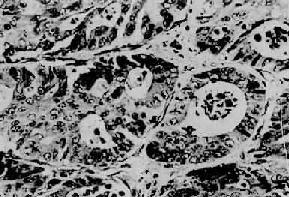

直肠腺<a href=癌"/>

图10-30 直肠腺

细胞分化较好,巢大多呈腺样结构(Ⅱ73-3057)